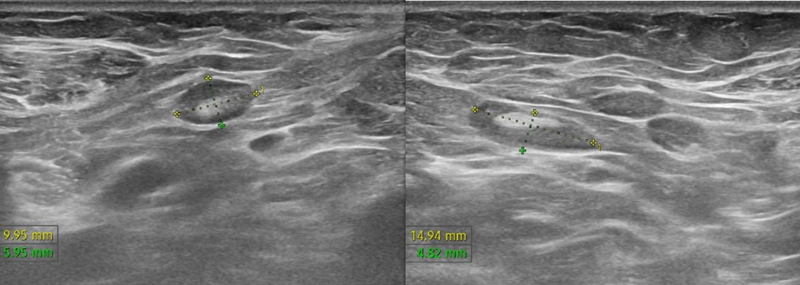

Trên siêu âm tuyến vú cho thấy hình ảnh nhân tuyến vú trái (BIRADS 5), kèm hạch hố nách hai bên.

Trên siêu âm cho thấy hình ảnh nhân tuyến vú trái (BIRADS 5), kèm hạch hố nách hai bên. Ảnh Medlatec